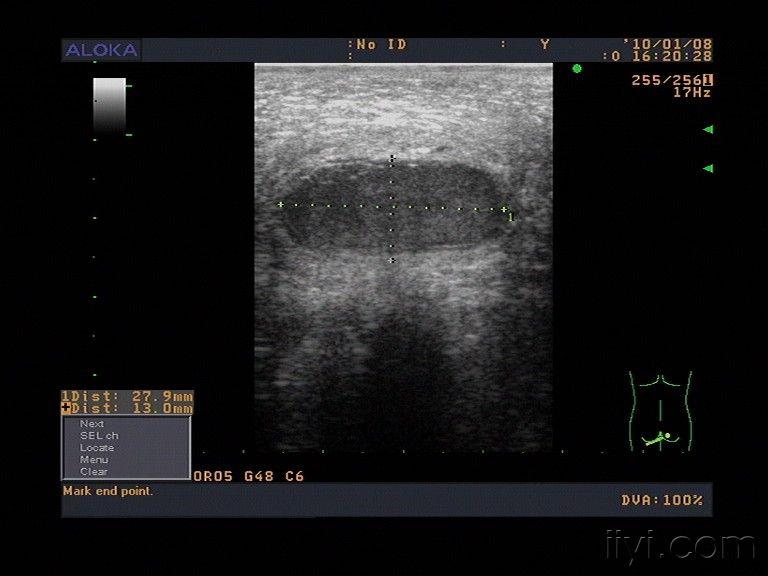

一症状表现坐骨结节囊肿通常表现为坐骨结节区域的疼痛肿胀和局部不适,尤其在久坐行走或压迫时症状加重严重情况下,可能因疼痛导致行走困难或无法正常坐下,影响日常生活二诊断方法诊断需结合身体检查如触诊判断囊肿位置大小及活动度和影像学检查如X光排除骨性病变,超声或磁共振成像明确囊。

坐骨结节囊肿的相关信息如下形成原因坐骨结节囊肿源于坐骨结节滑囊的长期反复摩擦和压迫这种刺激导致滑囊壁增厚,滑液分泌增多,最终形成囊性肿物常见于久坐长期卧床或臀部频繁受摩擦的人群,如办公室工作者司机或长期卧床患者症状表现患者通常在臀部下方触及肿块,伴有疼痛或酸胀感,久坐或。